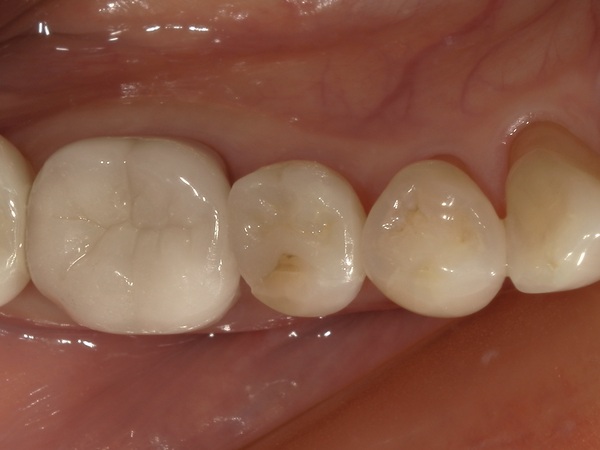

こちらが完成したセラミックインレーです。

適合・噛み合わせに問題がないことを確認し、歯科用セメントで装着しました。

治療後は不快症状もなく、経過は良好です。

お口を開けた際に気になっていた銀歯が自然な白い詰め物に変わり、患者様にも大変ご満足いただけました。